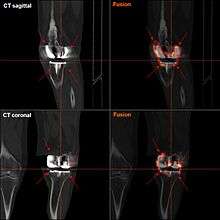

FDG-PET CT showing septic loosening of knee prothesis; the FDG-enrichment shows entensive inflammatory foci: demonstrative: the PET-image ist unlike the CT reconstruction not disturbed by the high radiation attenuation of the prothesis.